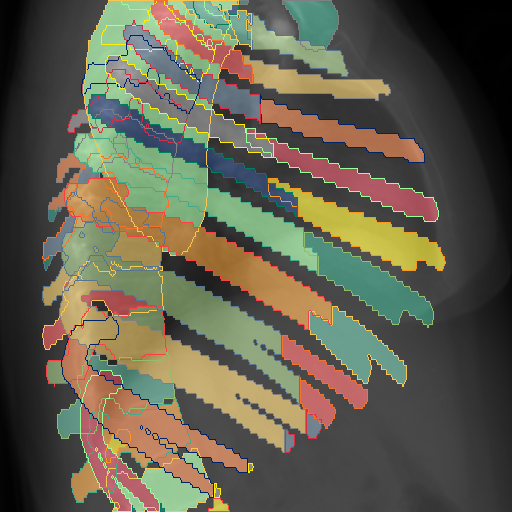

We show qualitative results for frontal projections in Fig. 2. We show a subset of classes belonging to the supercategories lungs, vascular systems, bones, and abdomen/digestive system. The predictions show minor deviations at the boundaries of the individual classes of the respiratory and vasculature system, while some inaccuracies become visible in the abdominal area. The qualitative results for the lateral projections are displayed in Fig. 2. Akin to the frontal view, the predictions show smoother borders but align with the ground truth. Apart from this, the segmentations provide matching insights on the thoracic anatomy with a slight deviation from the ground truth for both frontal and lateral views.

Fig. 2 shows quantitative segmentation results for frontal (top row) and lateral (bottom row) views. We display the class performances in the form of IoU (left), DICE (center), and Hausdorff distance (right) for each sample as a scatter plot with the mean performance for the classes shown by a line plot. Generally, we see performances for standard spinal classes, such as the thoracic vertebrae with average IoU-scores above 80%, while the average performance of rare vertebrae of the dataset belonging to the cervical and lumbar spine can drop down to 40%. In the frontal view, there exists more variance in thoracic vertebrae segmentation performance compared to the lateral view. Bone structures such as the sternum, clavicles, and scapula achieve IoUs in the mean from 85% to 95%. For ribs, we can see a noticeable performance drop for the anterior parts of the lower ribs independent of the side. The lower anterior ribs typically do not contain a large area, making them difficult to segment. This behavior is mirrored in the lateral view across the metrics. Abdominal classes can vary in segmentation quality as they occur in a nearly homogenous region. For example, while the liver or stomach are typically well-segmented, the duodenum and kidneys are more complex. Heart and Lung related classes show near-perfect segmentations with scores above 90% IoU. Breast tissue segmentation in comparison only achieves a mean of 70% mIoU. It can be noted that classes in the lateral view tend to have slightly better scores than their frontal counterparts.